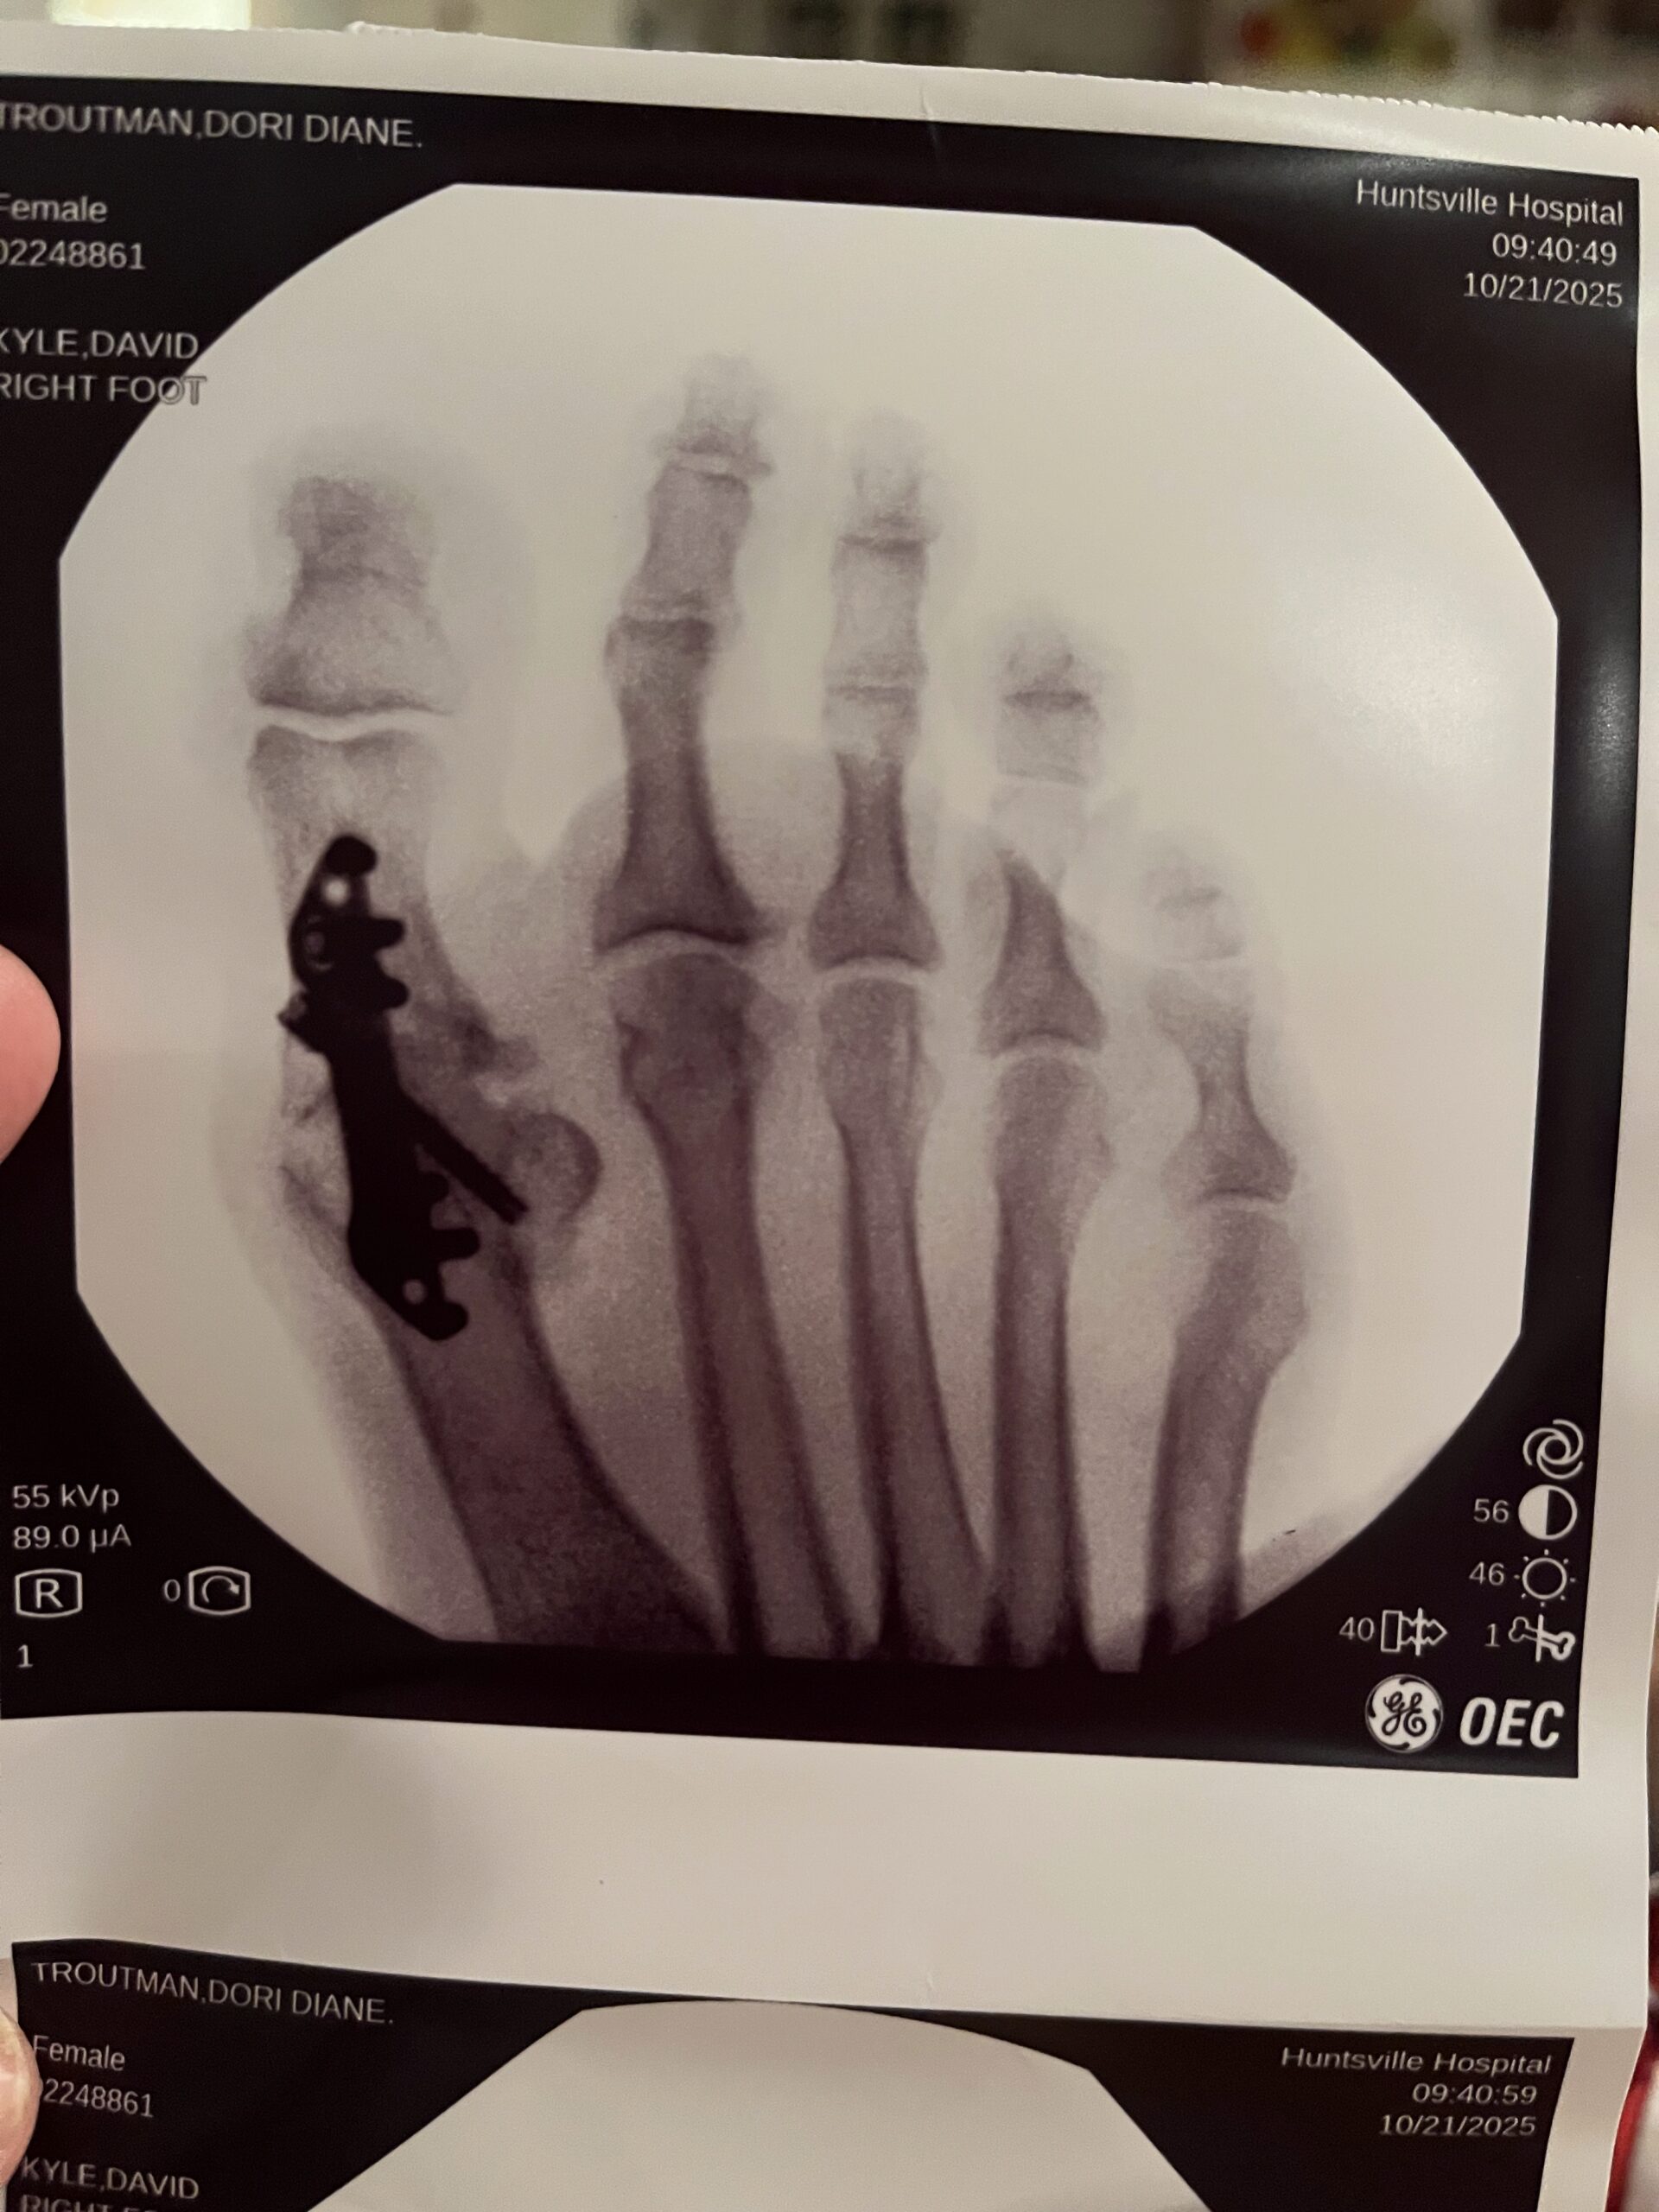

I’ve been dealing with some bone loss issues and pain in my big toe for quite some time but it never seemed like the right time to have the surgery… but finally back in the spring I decided October was the right season… our cut flower business would be over for the year, and I had a few months to clear my calendar for my small business of sewing and blogging. Also… the thought of laying on my porch bed curled up in a blanket and watching the leaves change seemed like the most soothing thing at the time!

So in October I had the surgery. And that began the first four weeks of hard! I can handle pain, I can handle inconvenience, I was prepared to not be able to drive for a few months, I even had emotionally prepared myself not to be able to go to my fitness classes or run.